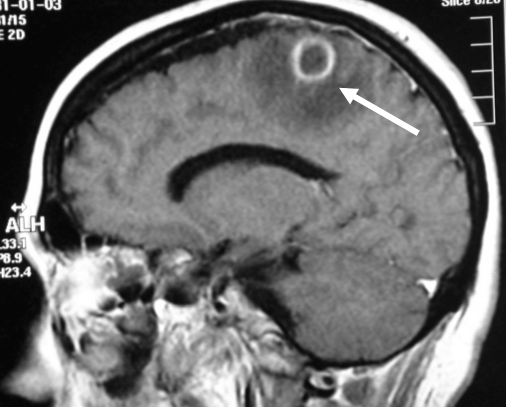

Absceso cerebral

Es una acumulación de células inmunitarias, pus y otros materiales en el cerebro, generalmente a raíz de una infección bacteriana o micótica.

Los abscesos cerebrales comúnmente ocurren cuando las bacterias u hongos infectan parte del cerebro. Como resultado, se presenta hinchazón e irritación (inflamación). Las células cerebrales infectadas, los glóbulos blancos, al igual que las bacterias u hongos vivos y muertos se acumulan en una zona del cerebro. Se forma tejido alrededor de esta zona y crea una masa o un absceso.